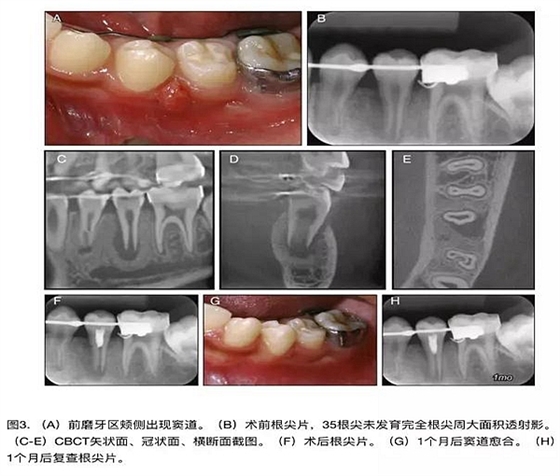

原則上年輕恒牙的牙髓治療應(yīng)盡可能以保存活髓的方式以便不影響牙根繼續(xù)發(fā)育。本文3個病例均描述了根尖尚未發(fā)育完成的下頜前磨牙被確診為牙髓壞死伴有大面積根尖病損,治療過程中在根管內(nèi)發(fā)現(xiàn)了部分活髓,而采用活髓切斷后都取得了很好的療效。